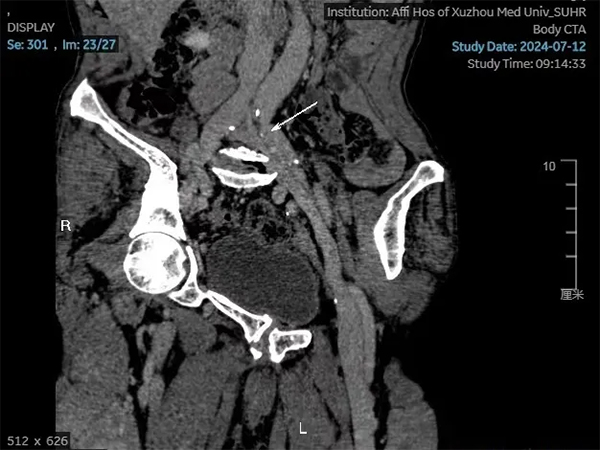

今年7月在兒子的陪同下戚大爺來到了徐州醫(yī)科大學(xué)附屬醫(yī)院介入放射科門診就診,也就是此次就診讓他的病情在30年后出現(xiàn)了轉(zhuǎn)機(jī)。在張慶橋主任的仔細(xì)詢問下,為其開具了相關(guān)檢查,下肢靜脈彩超顯示左下肢股靜脈及腘靜脈增寬伴靜脈瓣膜功能不全,CTA顯示左髂靜脈受壓。最終診斷為左髂靜脈壓迫綜合征。

圖2 左髂靜脈受壓狹窄伴管壁鈣化,遠(yuǎn)端靜脈增寬